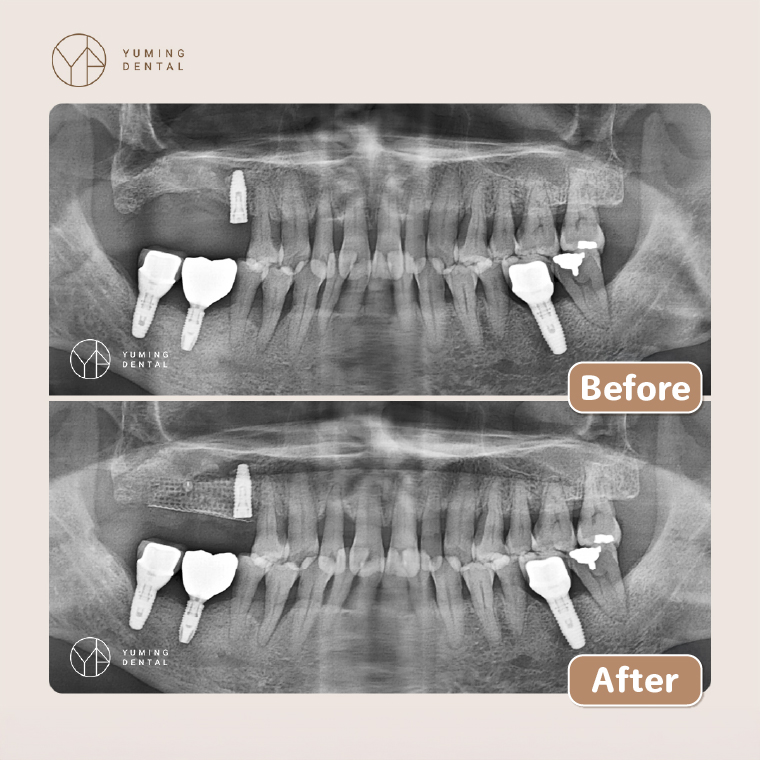

楊大為醫師提到,如今植牙補骨技術相當成熟,而讓他印象深刻的是1位年約70歲的美術老師,有抽菸習慣,15年前因牙周病拔掉多顆牙齒,當時需要大範圍補骨,必須在局部麻醉下從下巴取出1塊自體骨頭,才能補骨並進行4顆植牙。由於疏於保養,如今已有3顆損壞。所幸現今補骨技術已大幅進步,只須將智齒旁的碎骨屑混合大量骨粉,再放上鈦網覆蓋即可進行骨整合。

▲植牙補骨技術進步,使用碎骨屑與骨粉結合,再放上鈦網覆蓋即可進行骨整合,不必像以前那樣動大刀取骨。補骨前後X光對照,可見骨質恢復良好,植體穩固。(圖/祐民牙醫診所提供)